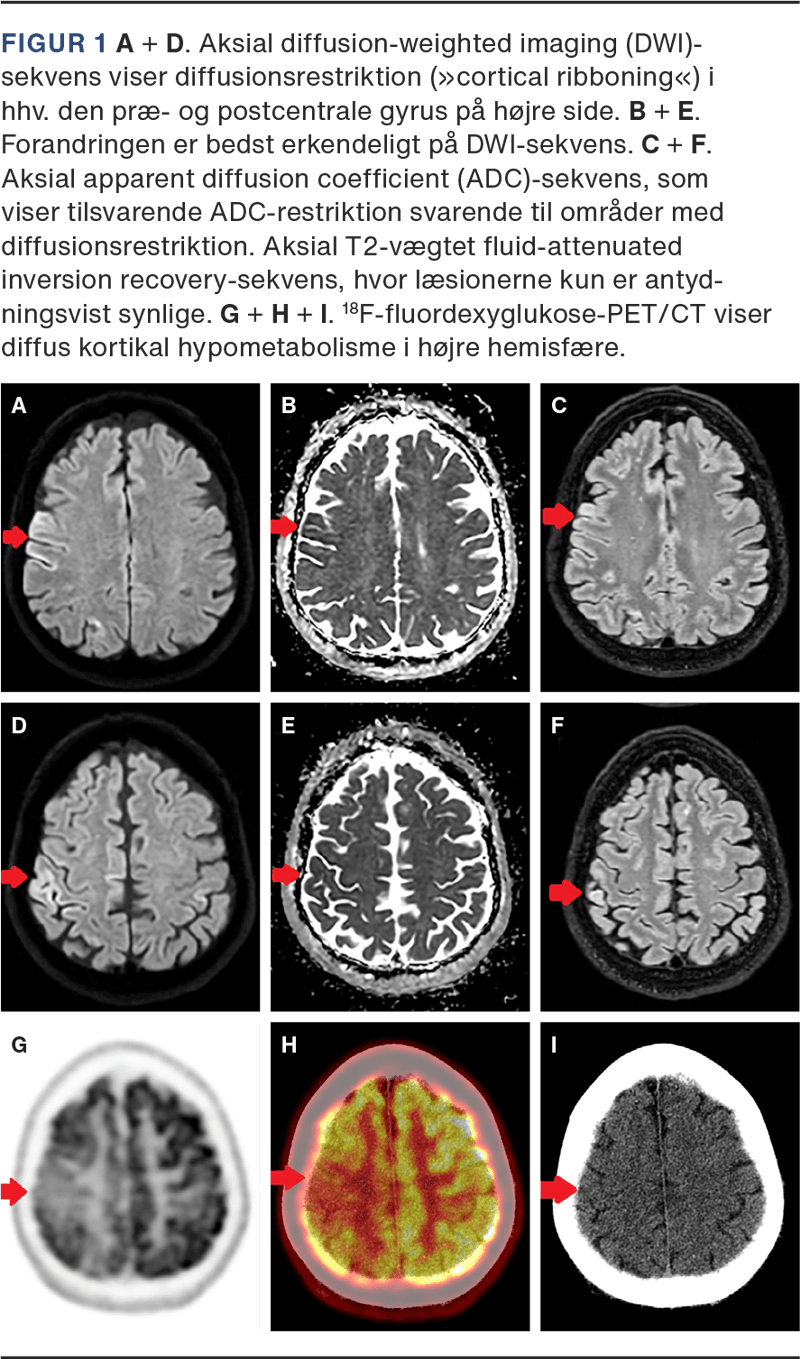

CT af cerebrum med henblik på apopleksi, blødning eller metastaser viste ingen patologiske fund. Supplerende MR-skanning af cerebrum med kontrast (Figur 1) viste kortikale diffusionsrestriktioner i diffusion-weighted imaging (DWI) med tilsvarende apparent diffusion coefficient-restriktion bilateralt, overvejende i højre hemisfære, især i højre centrale og subcentrale region, frontallap, insula, cingulum og venstre postcentrale region. Fund gav mistanke om tidligt stadie af CJD, men paraneoplastisk eller autoimmun encefalitis blev også overvejet som differentialdiagnoser. Det kortikale involveringsmønster uden basalganglieinvolvering var atypisk for CJD, men mistanken blev opretholdt, da læsionerne udelukkende involverede cortex, fordelt i et tilsyneladende tilfældigt mønster uden korrelat til vaskulære territorier.

En 18F-fluordexyglukose (FDG)-PET/CT (Figur 1) afkræftede recidiv af malignitet og viste nedsat kortikal metabolisme svarende til MR-forandringerne samt asymmetrisk lav aktivitet i højre thalamus, cingulum og occipitallap.

En MR-skanning af cerebrum er den foretrukne billeddiagnostikmodalitet på grund af dens stærke korrelation med kliniske og neuropatologiske fund. En MR-skanning kan påvise karakteristiske ændringer allerede tre uger efter symptomdebut [3] og kan identificere abnormiteter, selv før fremkomsten af karakteristiske eeg-forandringer [4]. Typiske MR-fund inkluderer involvering af basalganglierne samt hyperintensitet i DWI-, fluid-attenuated inversion recovery- og T2-vægtede sekvenser i cerebral cortex, kendt som »cortical ribboning« [2]. DWI-sekvensen er den mest følsomme [2-4] med en sensitivitet på 91% og en specificitet på 97% [4]. MR-forandringerne, ligesom symptomerne, er ofte asymmetriske tidligt, men bliver mere bilaterale senere.

18F-FDG-PET/CT kan bidrage til diagnosen ved at differentiere sCJD fra andre demenssygdomme gennem påvisning af diffus kortikal hypometabolisme og basalganglieforandringer [5].